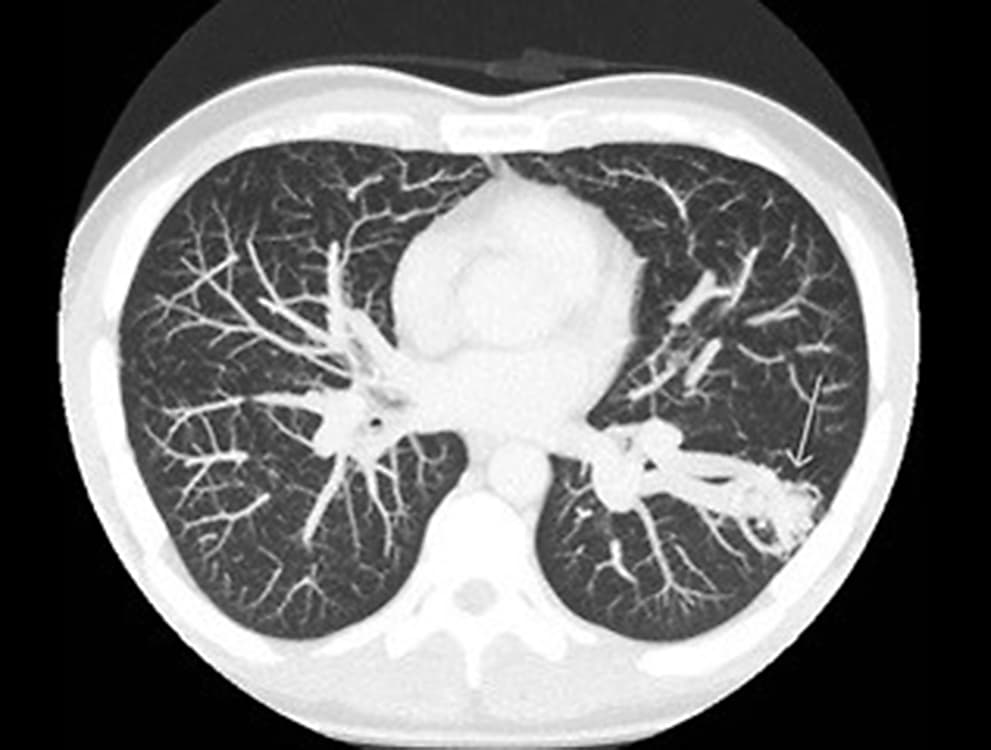

Som led i udredningen blev der foretaget CT af thorax/abdomen, hvorved man fandt en pulmonal arteriovenøs malformation (PAVM) i venstre lunges underlap (pil på billedet). PAVM er sjældent forekommende og hyppigt forårsaget af den arvelige sygdom heriditær hæmoragisk telangiektasi (HHT) (morbus Osler) [1]. Patienten blev henvist til HHT-centeret i Odense og diagnosticeret med HHT-2. Prævalensen af HHT i Danmark er 1:6.500, og hos ca. 30% af dem kan man finde en PAVM [2]. Risikoen for cerebral absces hos personer med ubehandlet PAVM er mere end 100 gange højere end risikoen hos baggrundsbefolkningen [3]. Det er derfor relevant at overveje PAVM og HHT hos unge, ellers raske patienter, som får cerebral absces.